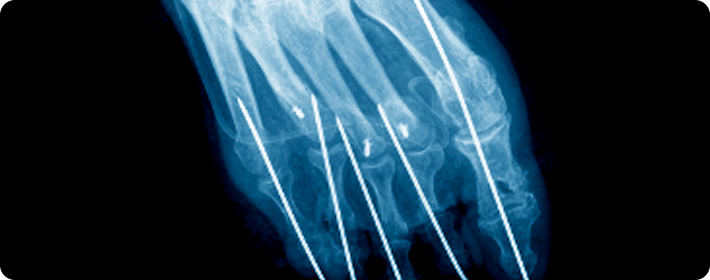

수근관 유리술

손목의 수근관을 절개해 정중 신경을 압박하는 인대를 풀어주는 수술입니다. 손의 저림, 통증, 감각 저하 등의 증상을 완화하고 손 기능을 회복하는 데 도움을 줍니다.

활차 유리술

손가락 힘줄을 둘러싼 활차(힘줄이 통과하는 섬유띠)를 절개하여 치료하는 수술입니다. 힘줄이 원활히 움직이도록 눌린 부위를 풀어 손가락의 통증과 움직임 장애를 개선합니다.